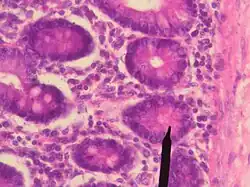

Человеческие клетки Панета

Клетки Панета — клетки тонкой кишки, обеспечивающие антибактериальную защиту. Названы в честь австрийского врача Йозефа Панета. Функционально схожи с нейтрофилами. При столкновении с бактериями или бактериальными антигенами выделяют антимикробные вещества в просвет крипты, способствуя поддержанию кишечного барьера.